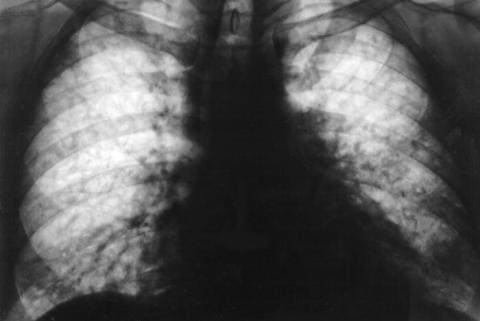

Пневмония – воспаление легочной ткани, основная масса которой вызывается бактериями, в частности пневмококком, однако встречаются и пневмонии другой этиологии. Основными жалобами являются повышение температуры тела от субфебрильной до фебрильной, нарастающая слабость, снижение аппетита, озноб и повышенная потливость, общее недомогание, усиливающийся кашель продуктивного характера (с мокротой). Характер мокроты будет полностью зависеть от причины, вызвавшей заболевание (более подробно в статье: пневмония).

Пневмония

слизистой гортани, трахеи), бронхоскопия, рентгенологическое исследование легких (выявление характера процесса при бронхите, пневмонии, степени распространения воспаления, динамики лечения).